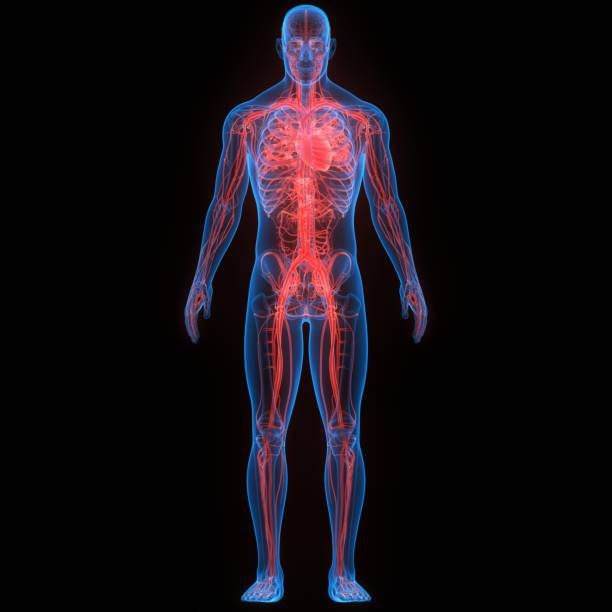

Proper body alignment improves posture, reduces pain, enhances movement efficiency, prevents injury, supports balance, breathing, flexibility, and long-term musculoskeletal health.